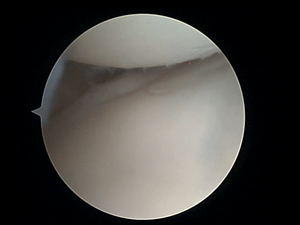

Wrist arthroscopy (from the Greek άρθρωση, arthros "joint" and σκοπεῖν, skopein "to look or see") can be used to look inside the joint of the wrist. It is a minimally invasive technique which can be utilized for diagnostic purposes as well as for therapeutic interventions. Wrist arthroscopy has been used for diagnostic purposes since it was first introduced in 1979. However, it only became accepted as diagnostic tool around the mid-1980s. At that time, arthroscopy of the wrist was an innovative technique to determine whether a problem could be found in the wrist. A few years later, wrist arthroscopy could also be used as a therapeutic tool.[1]